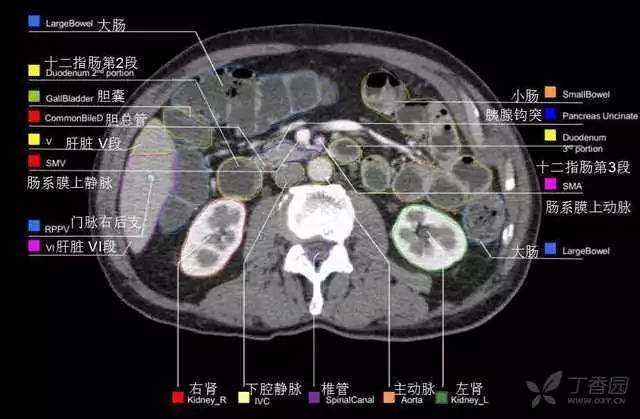

腹部肝脏高清CT断层的图谱

全腹部高清CT图谱,淋巴结彩色图谱,血管解剖图谱大汇总!

肝段,肝内管道的分布规律